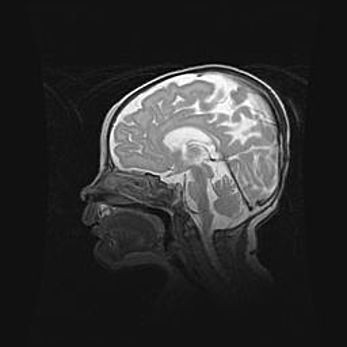

Неполная лизэнцефалия (пахигирия). Открытая гидроцефалия.

Возраст: 17 дней

Вес: 3110 г

Пол: мужской

Окружность головы: 33,5 см

Срок гестации: 35-36 недель

Лизэнцефалия—недоразвитие корковой пластинки и мозговых извилин в результате нарушения миграции нейронов коры. Поверхность мозговых полушарий гладкая. Микроскопически выявляется отсутствие нормальных слоев коры и скопление групп нейронов в подкорковом белом веществе.

Пахигирия—уменьшение числа вторичных извилин. В пораженном полушарии нервные клетки образуют толстый недифференцированный слой с неправильно расположенными нервными волокнами и группами гетеротопных клеток. Нервные клетки незрелые. Белое вещество истончено. При этом нередко аномально развит корково-спинномозговой путь.